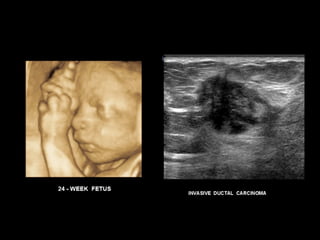

ULTRASONOGRAFIA

* 3 to1 MHz extended operating frequency range *2D, Live 3D Echo, Color Doppler with 2D, biplane and 3D  Adult and pediatric cardiology applications   *10 to 5 MHz extended frequency range *Biplane (transverse and sagittal) Steerable pulsed Doppler, Color Doppler, and imaging Endocavitary applications including urology, endorectal and endovaginal *Supports transrectal biopsy procedures